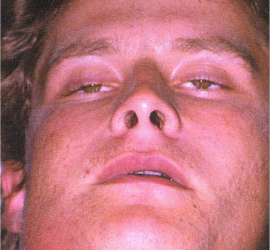

Этиология и патогенез. Возникает при осложнениях периодонтитов моляров, остеомиелита угла и ветви челюсти, из-за заноса инфекции при инъекции анестетиков. Клиническая картина. Появляется боль при открывании рта, затем при глотании. Асимметрия лица незначительная, так как инфильтрат располагается за ветвью нижней челюсти. Повышение температуры тела до 38—39° С, контрактура жевательных мышц, увеличение […]